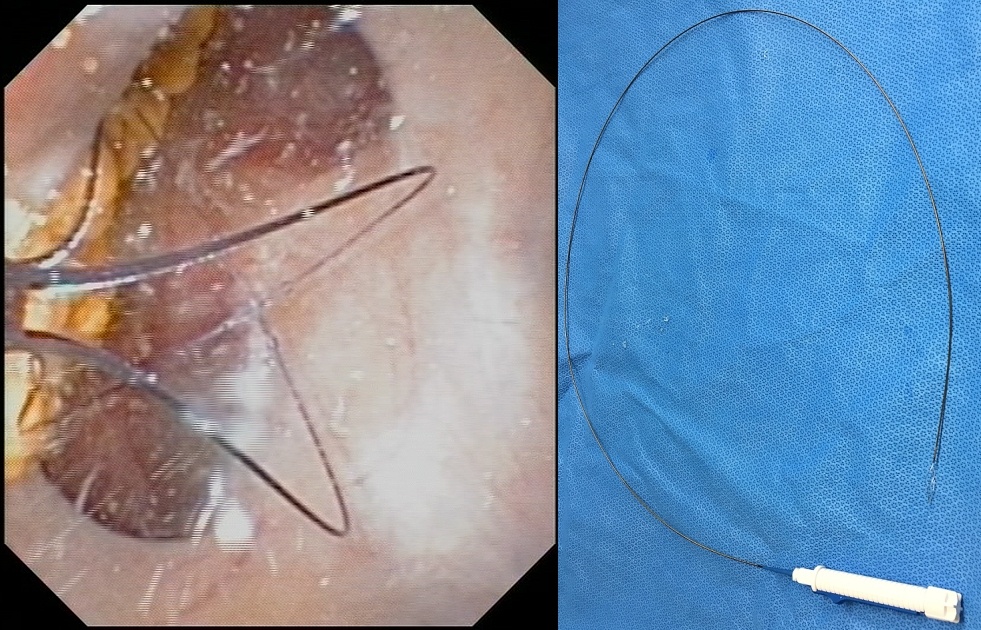

Es handelt sich hierbei um ein flexibles Endoskop (Abbildung 4), mit dem Harnsteine im gesamten Nierenbeckenkelchsystem geborgen werden können (Abbildung 5). Auch hier wird das Bild mittels integrierter Kamera auf eine Videoeinheit übertragen. Um den intrarenalen Druck und die Gefahr der Harnleiterverletzung während der Operation möglichst gering zu halten, empfiehlt es sich, Harnleiterschleusen zu benutzen. Hierdurch wird die Sicht verbessert und der Zugang zum Stein erleichtert [16, 11]. Auch hier stehen

Instrumentengang eines flexiblen Ureterorenoskops eingeführt wird;

rechts in situ

Hilfsmittel wie Körbchen aus Nitinol[2] (Abbildung 6) und der Holmium-Laser zur Steinextraktion bzw. Steinzertrümmerung zur Verfügung.